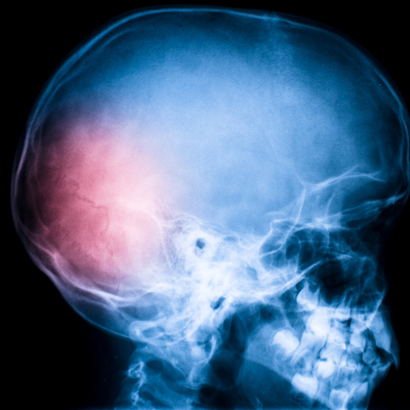

Omega-3: nueva terapia potencial para la recuperación de traumatismos craneales

Publicados los resultados del primer estudio que demuestra los beneficios de Omega 3 en el cerebro durante la convalecencia tras un traumatismo craneal. Los Omega 3 podrían ser útiles para reducir los efectos negativos a largo plazo sobre el cerebro de un traumatismo craneal. En concreto, según los expertos, los mayores efectos podrían conseguirse administrando estos ácidos grasos al paciente ya en urgencias. Así lo sugirieron Michael Lewis, Parviz Ghassemi y Joseph Hibbeln, autores de un estudio publicado en el American Journal of Emergency Medicine1 en el que, por primera vez, se comprobaron los efectos de la administración de Omega-3 durante la convalecencia tras un traumatismo craneoencefálico.

En los últimos años, también ha aumentado el interés por los posibles beneficios de estos nutrientes tras un traumatismo craneoencefálico, una de las principales causas de muerte y discapacidad traumática. La mortalidad asociada a este tipo de traumatismos se ha reducido mucho gracias a los avances en los métodos quirúrgicos y de cuidados intensivos, pero aún no existen terapias específicas para afrontar la fase de recuperación. De hecho, la recuperación pasa por un periodo en el que el cerebro tiene que lidiar con problemas como lainflamación y la presencia de radicales libres. En 2010, el Instituto de Medicina de Estados Unidos (IOM) nombró al Omega-3 como una de las moléculas cuyos beneficios deberían probarse en esta fase de convalecencia, y el estudio de Lewis y sus colegas es el primero que intenta arrojar luz sobre este potencial. Los investigadores administraron altas dosis de estos ácidos grasos a un adolescente que se recuperaba de un grave accidente de moto. En concreto, 10 días después del traumatismo craneal, el chico recibió 9,756 gramos de EPA (ácido eicosapentaenoico) y 6,756 gramos de DHA (ácido docosahexaenoico), los principales Omega-3 de origen alimentario. La terapia, explicaron los autores, produjo mejoras graduales tanto en el aspecto cognitivo como en el físico, hasta el punto de que tres meses después del accidente el chico se graduó y cuatro meses después del traumatismo pudo volver a casa, donde continuó la terapia durante todo el año siguiente.